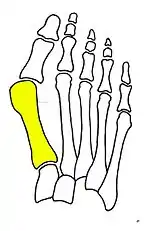

Primus varus deformity is the leaning of the first metatarsal bone away from the second metatarsal and towards the opposite foot (Fig. 1). As it leans over, its head sticks out to form the bunion bump and it also widens the forefoot to cause shoes feeling too tight. Thus when bunion pain becomes unmanageable, surgical correction is to narrow the forefoot by repositioning of the first metatarsal head back to its normal position. This can be done by osteotomy (bone-breaking), soft tissue (non-osteotomy) or fusion techniques.

Syndesmosis procedure addresses specifically the two fundamental problems of metatarsus primus varus deformity that gives rise to the bunion deformity. They are leaning and instability of the first metatarsal bone . Syndesmosis procedure uprights the leaning first metatarsal bone with strong binding sutures between it and the second metatarsal bone (Fig. 2) and then also stabilizes it uniquely by creating a fibrous connecting bridge between these two bones (Fig. 3, 4). First metatarsal bone can be readily realigned because by definition of the metatarsus primus varus deformity its first metatarsal is abnormally loose and mobile.